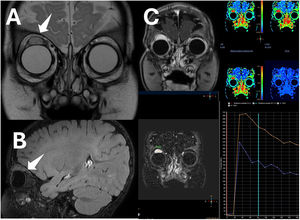

Imágenes de resonancia magnética. En plano coronal (A) y sagital (B) se observa lesión homogénea hiperintensa en T2 en la parte distal del recto superior del ojo derecho, cerca de la inserción ocular, de 16×14×16mm (diámetros ap×tr×cc), con un borde hipointenso correspondiente a una pseudocápsula, con una difusión facilitada y sin calcificación ni hemorragia dentro de la lesión. C. Se realizó estudio de contraste dinámico, donde se adquirieron imágenes T1 con supresión grasa, observándose una curva arterial/tipo 3 que muestra un rápido ascenso inicial, seguido de un descenso con el tiempo (washout) en la fase retardada. La imagen poscontraste en el músculo recto superior izquierdo muestra un realce homogéneo.